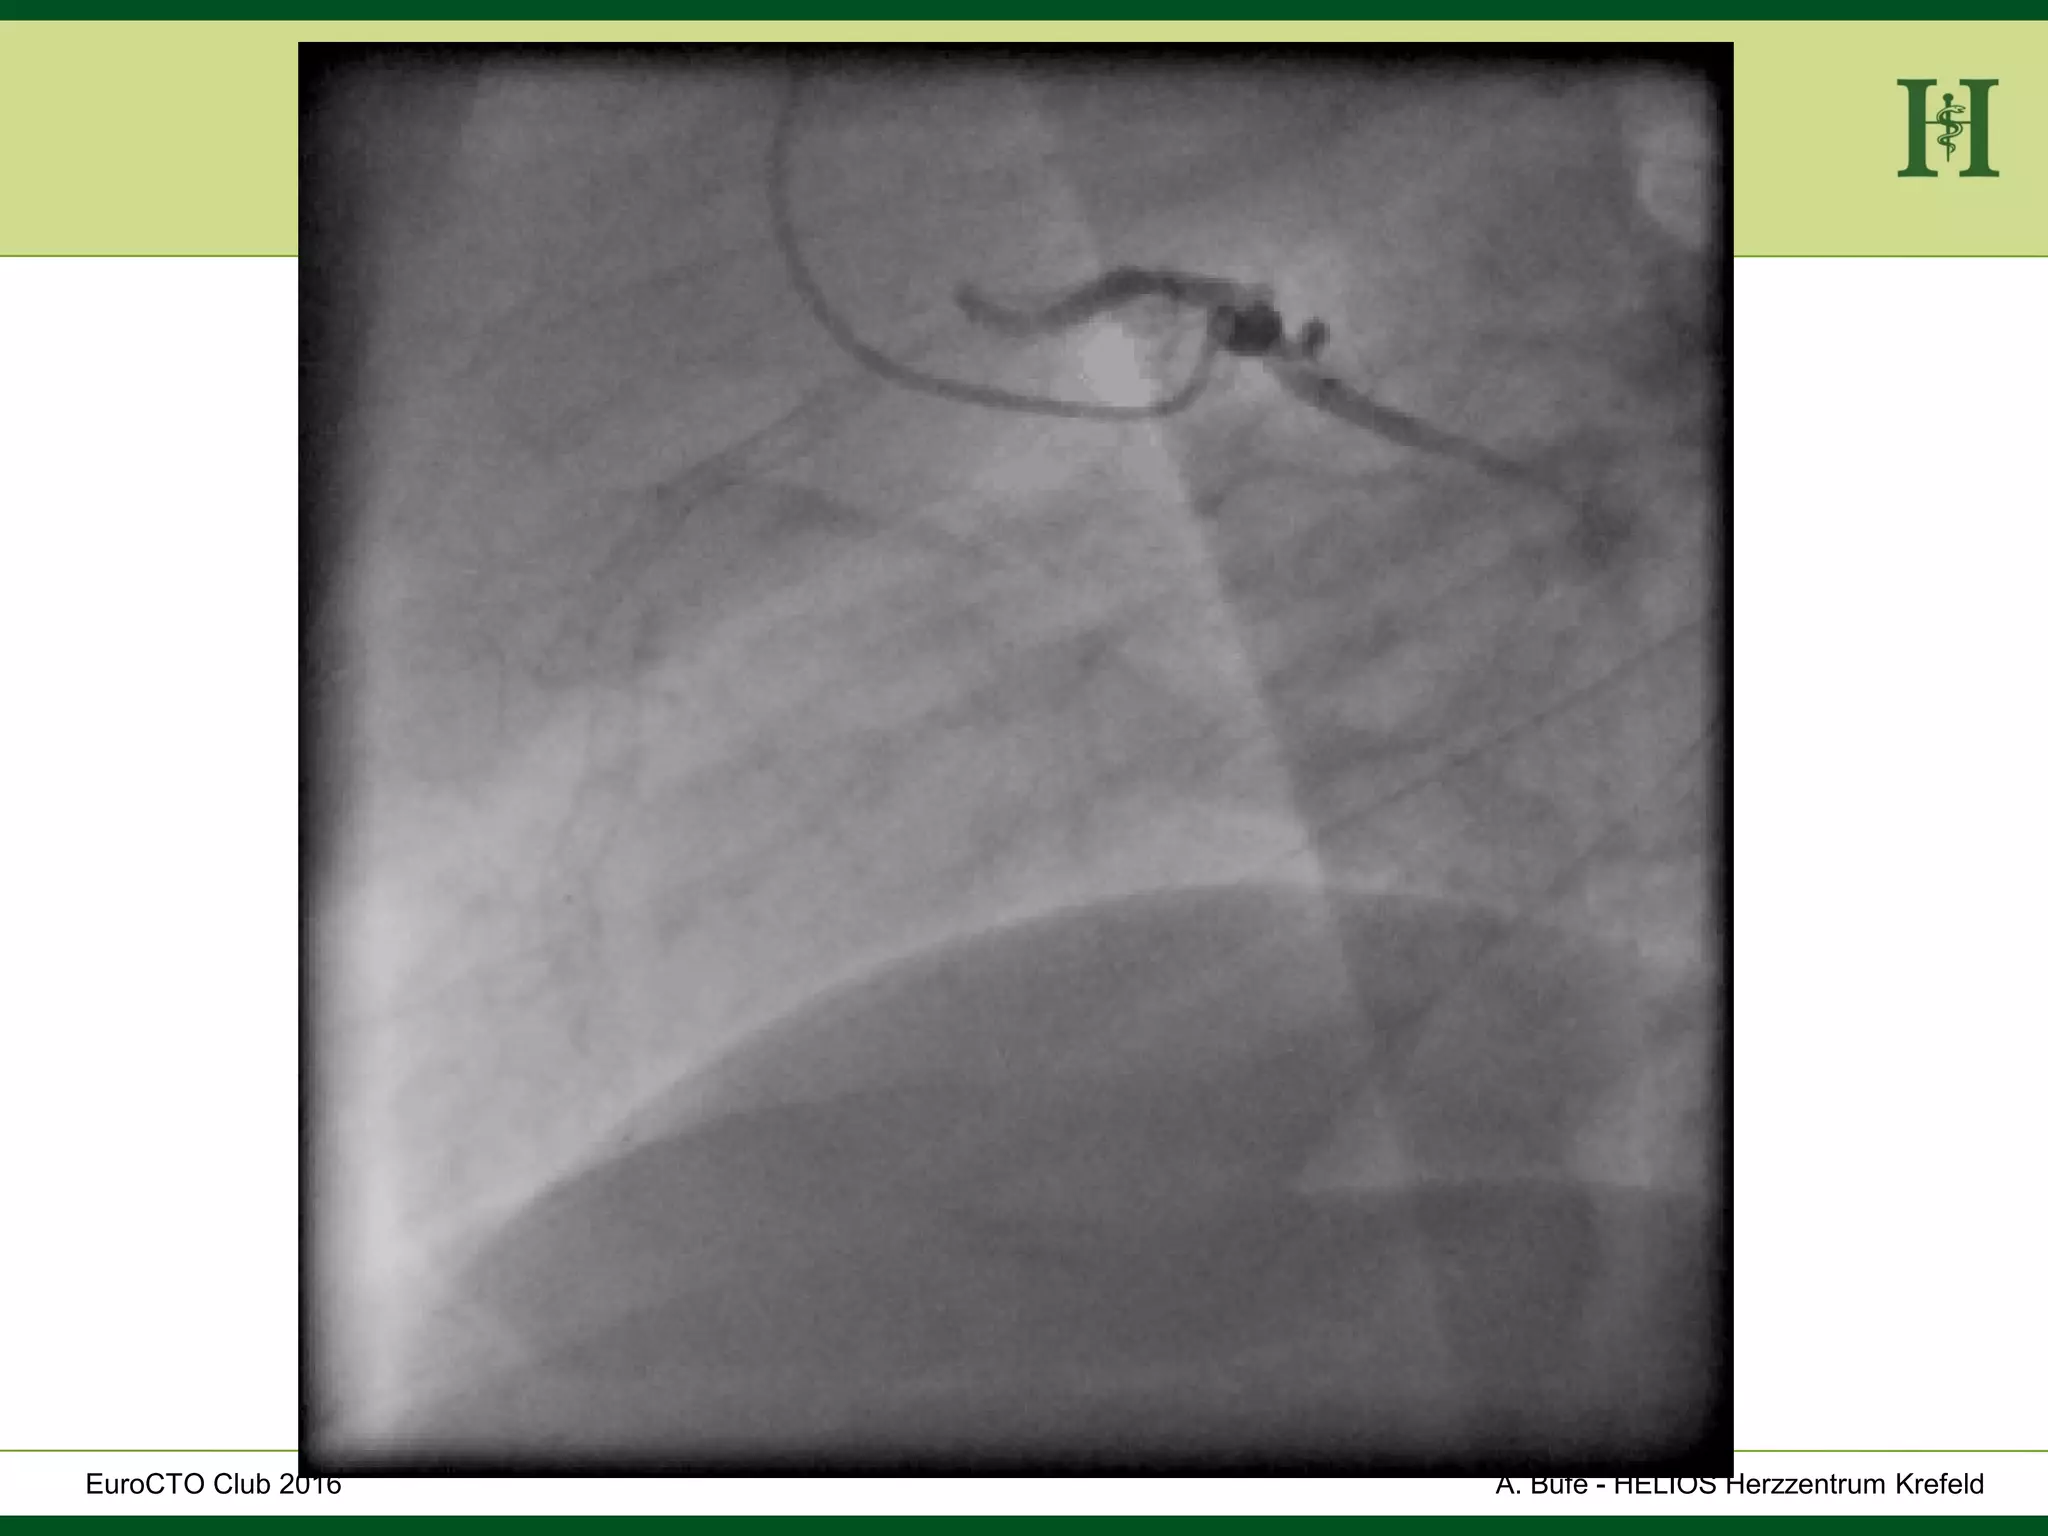

Hard

occlusion